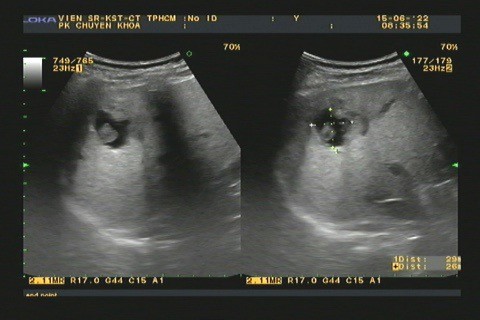

- Chẩn đoán hình ảnh: siêu âm, chụp CT phát hiên những tổn thương và biến chứng gan mật.

Hình 2.Tổn thương gan ở bệnh nhân bị nhiễm sán lá gan nhỏ